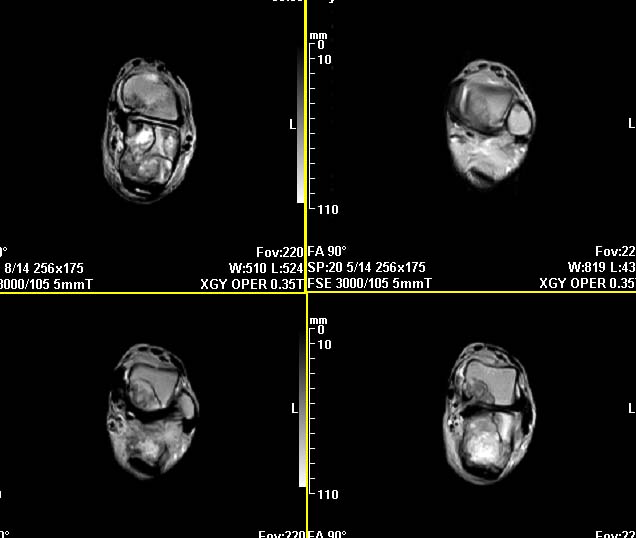

m,9y,左足肿痛半年,无皮肤发红,诱因为外伤后起因。无发烧,无其他疾病。临床考虑多发血管瘤。mri增强后有强化,请分析。是骨髓瘤吗?

左足多发囊状膨胀性骨质破坏,边较清,关节间隙及软组织未见明显异常。结合临床。可排除炎症性病变。病变中心为骨髓腔。有强化。中心坏死。嗜酸性肉芽肿可能大。

今天从天津肿瘤医院传来消息:病理结果是非骨化性纤维瘤。

为啥没有平片呢?平片就能诊断了吧

平片也诊断不了,这种非骨化性纤维瘤实在是太罕见了,如果资料全,病理可靠,可以作一个病例报道了。